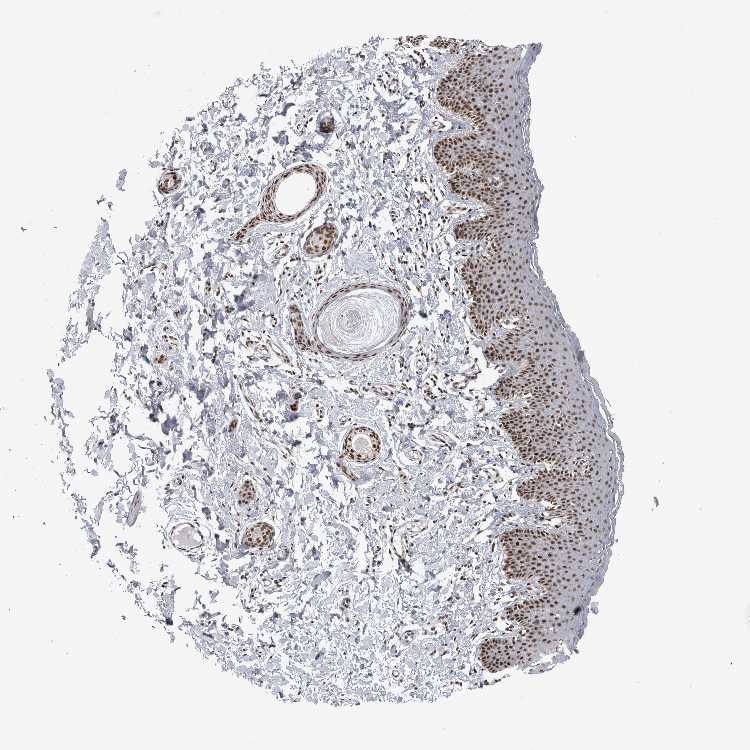

SKIN 1 - Antibody stainingi

Antibody staining in the annotated cell types in the current human tissue is reported as not detected, low, medium, or high, based on conventional immunohistochemistry profiling in selected tissues. This score is based on the combination of the staining intensity and fraction of stained cells.

Each image is clickable and will lead to virtual microscopy that enables deeper exploration of all samples and also displays staining intensity scores, fraction scores and subcellular localization as well as patient and tissue information for each sample.

Antibody HPA024331

Langerhans High

Fibroblasts High

Keratinocytes High

Melanocytes High

SKIN 2 - Antibody stainingi

Epidermal cells High